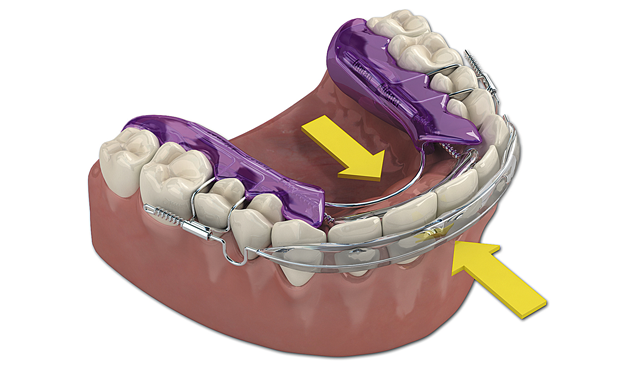

The illustration in Figure 5 shows the action of the Inman Aligner. The facial bow is powered by springs pulling it lingually and lingual bow is powered by springs pushing the teeth facially. Rarely is it necessary to adjust the appliance itself. The adjustments are made to interproximal areas of the teeth.

Fig. 5